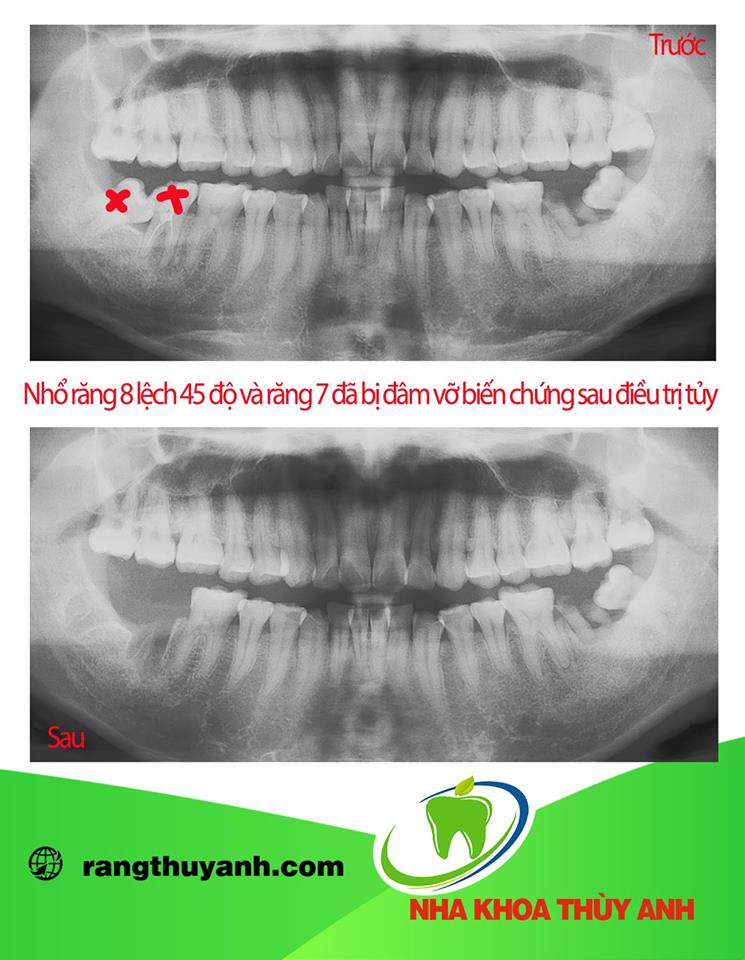

Răng khôn mọc lệch 45 độ là một trong những trường hợp xảy ra phổ biến khi mọc răng khôn. Khi bị răng khôn mọc lệch 45 độ nếu không xử lý có thể sẽ ảnh hưởng đến chức năng ăn nhai, ảnh hưởng đến chất lượng cuộc sống cũng như sinh hoạt hàng ngày của bạn. Vậy khi có răng khôn mọc lệch 45 độ chúng ta nên làm gì, mời các bạn theo dõi bài viết dưới đây nhé.

Có rất nhiều phân loại răng khôn khác nhau như phân loại của Winter, phân loại của Pell & Gregory. Tại Việt Nam trong các bảng giá nha khoa hẳn nhiên các bạn sẽ thấy có những hạng mục như nhổ răng khôn mọc kẹt, mọc lệch 45 độ, răng khôn nằm ngang, răng khôn mọc ngầm. Giới chuyên môn thường sẽ tìm những phân loại học thuật, để từ phân loại hình dung dễ dàng luôn quy trình điều trị. Tuy nhiên bệnh nhân thì chỉ cần biết những phân loại rất đơn giản , như phân loại trong bảng giá cũng được.

Răng khôn hay còn gọi là răng số 8 là răng hàm lớn số 3 là răng mọc cuối cùng, khi các răng khác đã mọc ổn định trên cung hàm. Răng khôn mọc trong khoảng từ 18 đến 25 tuổi. Hầu hết răng khôn mọc trong khoảng không gian nhỏ do bị giới hạn, nên thường bị mọc kẹt, mọc lệch, mọc ngầm.